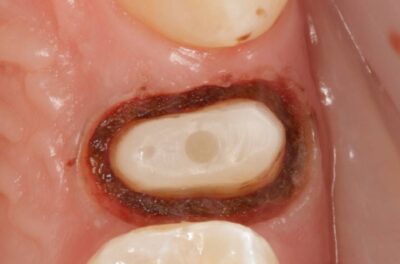

Специализация: терапия(эндодонтия), ортопедия, имплантология.